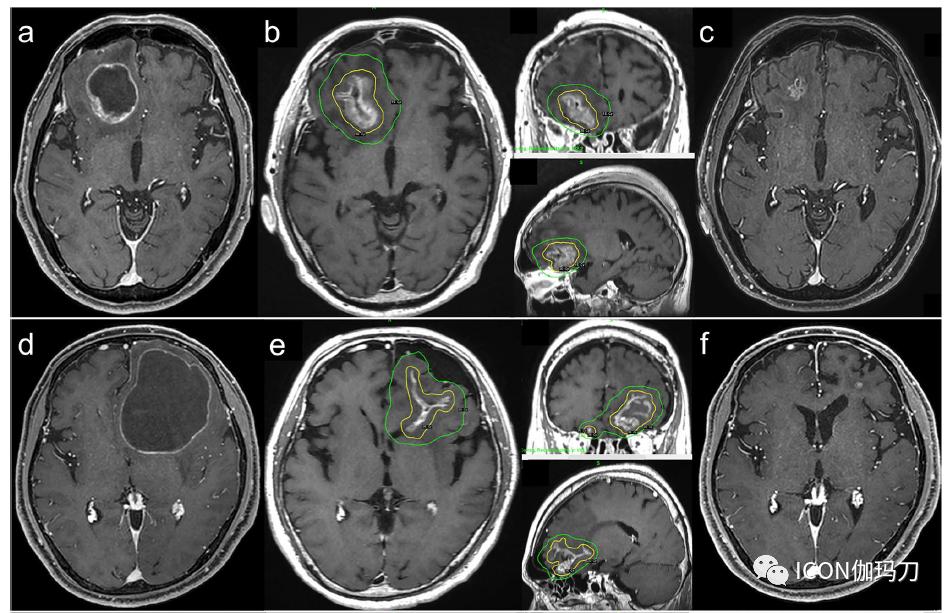

图3轴位增强T1加权磁共振成像(CE-MRI)图像显示位于右侧额叶的一个大的囊性转移(41x36x37 mm, 26.4 mL)。b Ommaya贮液囊抽吸后缩小囊性病变的GKRS剂量计划图像。黄线表示30-Gy的边缘,蓝线表示20-Gy的边缘。最大剂量为42.9 Gy。c GKRS后28个月,肿瘤得到控制。d轴位增强MRI示左侧额叶大的囊性脑转移瘤(79x48x67 mm, 110.8 mL)。e 从Ommaya贮液囊抽吸后缩小囊性病变的GKRS剂量计划图像。黄线和蓝线分别表示35-Gy和20-Gy的边界。最大剂量为48.6 Gy。f GKRS后25个月,肿瘤得到控制。g轴位增强MRI示右侧颞叶大囊性脑转移瘤(28x31x29 mm, 39.4 mL)。h 从Ommaya贮液囊抽吸后缩小囊性病变的GKRS剂量计划图像。黄线和蓝线分别表示35-Gy和20-Gy的边缘。最大剂量为47.3 Gy。i GKRS后10个月,肿瘤得到控制。